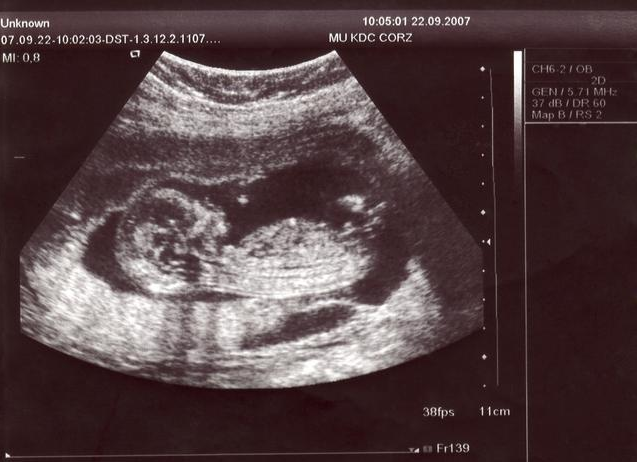

四維彩超是一種先進(jìn)的醫(yī)學(xué)成像技術(shù),能夠在孕期實(shí)時(shí)觀察胎兒的發(fā)育情況,與傳統(tǒng)的二維、三維彩超相比,四維彩超能夠提供更清晰、更立體的圖像,讓準(zhǔn)父母更直觀地了解胎兒的成長(zhǎng)過程。

2、觀察圖像:在四維彩超圖像上,男性胎兒的生殖器官呈現(xiàn)為細(xì)小的小雞冠狀結(jié)構(gòu),而女性胎兒的生殖器官則呈現(xiàn)為較為平滑的橢圓形結(jié)構(gòu),通過觀察這些特征,可以初步判斷胎兒的性別。

圖解展示

(此處可插入一系列四維彩超圖像,展示男性胎兒和女性胎兒生殖器官的不同特征)